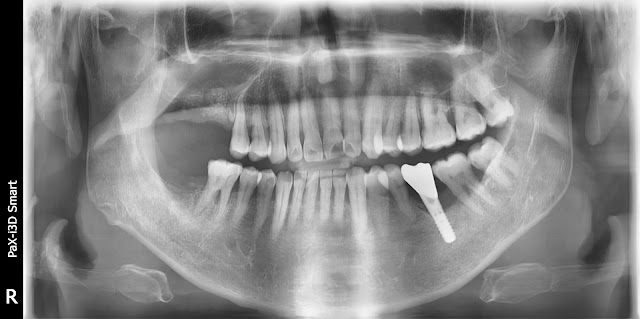

This is a 61-year-old male patient.

Socket management was performed at the same time as tooth number 16 was extracted.

This photo is about 4 months after tooth extraction.

Strauman BLT was implanted using bone grafting using a crestal approach using the usual method.

Because the initial fixation was not good, the prosthesis was completed after about 6 months.

However, about 6 months after functioning, the implant was shaken like this and was removed.

After about 5 months, additional cresatal approach and bone grafting were performed again for the first time. Strauman BLX was placed to provide better fixation.

About 4 months later. Progressive loading was performed by installing a temporary prosthesis.

After about 3 months, the final prosthesis was performed.